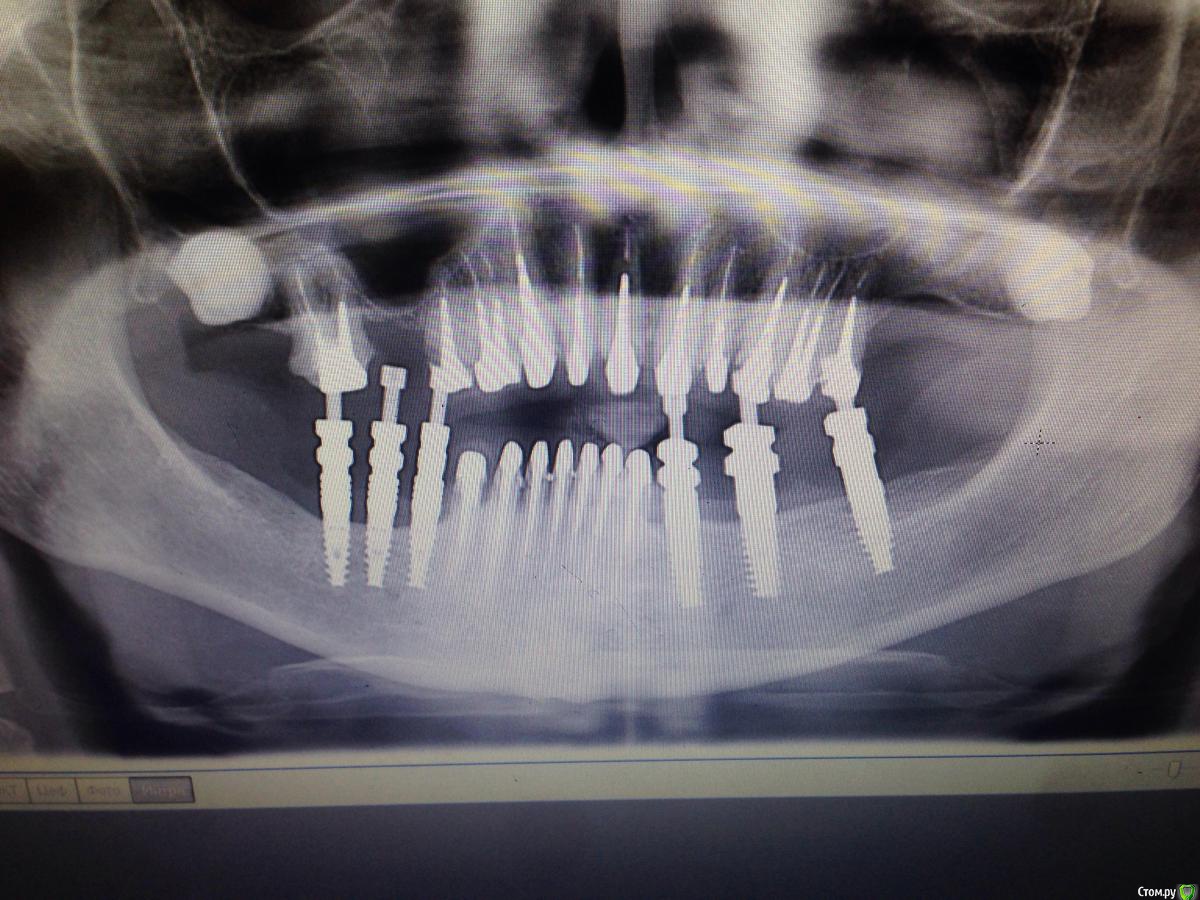

Bratok Опубликовано 17 июля, 2016 Поделиться Опубликовано 17 июля, 2016 Коллеги, всем привет! Вот такая пациентка в клинике был доктор у нас с 20 летним стажем, она уехала сейчас и не работает. Протезировала пациентку.. Были изготовлены временные коронки.. Судя по всему страдал герметизм и под ними все печально.. Десне и феррулу хана...Чтобы Вы тут посоветовали? Планировалось к нее мк... Сделать в 3 сегмента 3-3 и остальные блоком. Какой прогноз? Лет 5? Извиняюсь за качество rg.. Ссылка на комментарий

AndyAndy Опубликовано 17 июля, 2016 Поделиться Опубликовано 17 июля, 2016 Привет! М-да, печаль беда.... Мы же с вами понимаем что все это надо извлекать, убирать кариес и смотреть на то что останется. Возможно хир удлинение коронковой части. Пациентка как настроена вообще? вы наверняка объяснили ей чем она рискует. Но все- таки стремно так все оставлять. Там герметизм нарушен и между вкладками и стенками канала, 100%. Ссылка на комментарий

Evgen-Vozhd Опубликовано 16 августа, 2016 Поделиться Опубликовано 16 августа, 2016 Объяснил бы ситуацию пациентке.делал бы все одиночками. по мере вылета зубов в будущем доставлять имплантаты. Или вариант 2: extr. всех зубов , имплантация в позицию 11,13,14,16,21,23,24,26, 42,32, времянки на импланты во фронт, одномоментное постоянное протезирование Ссылка на комментарий

korotkevich Опубликовано 17 августа, 2019 Поделиться Опубликовано 17 августа, 2019 (изменено) Коллеги, всем привет! Вот такая пациентка в клинике был доктор у нас с 20 летним стажем, она уехала сейчас и не работает. Протезировала пациентку.. Были изготовлены временные коронки.. Судя по всему страдал герметизм и под ними все печально..Десне и феррулу хана...Чтобы Вы тут посоветовали?Планировалось к нее мк...Сделать в 3 сегмента 3-3 и остальные блоком. Какой прогноз? Лет 5?Извиняюсь за качество rg..В идеале доставать вкладки, убирать кариозные ткани, делать билдапы и затем либо хирургическое удлинение, либо вертипреп, либо и то, и другое; и металлокерамические коронки с гирляндой, таким образом сохраните максимально то, что есть Изменено 17 августа, 2019 пользователем korotkevich Ссылка на комментарий